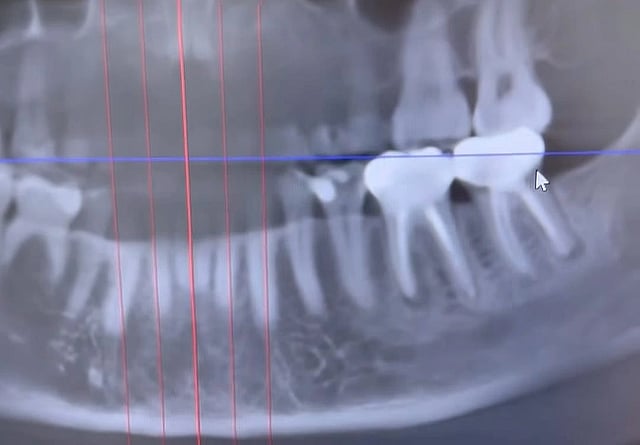

A screengrab of the oral x-ray from the viral video shows a black and white radiographic image of the lower and upper teeth and a portion of the surrounding jawbone. Two lower molar teeth root canals are seen as opaque as a result of root canal treatment. There are blackish shadows around the roots of these two teeth.  @livingwellwithdrmichelle/Instagram

Dr. Michelle Jorgensen, DDS, a dentist in Utah, shared Jacobsen’s x-ray scan online, showing two infected root canals.

According to Newsweek, before Jacobsen’s cancer diagnosis, she had occasionally noticed a subtle, painless, "puffy," almost "squishy" feeling in the gum beneath one of her root canals. After she was diagnosed with invasive ductal carcinoma (IDC), the most common type of breast cancer, and a blood test revealed signs of infection in her bloodstream, her naturopath doctor suggested a dental checkup. Advanced imaging showed both of her root-canal-treated teeth were infected and had abscesses beneath them. After extracting the teeth on October 13, the oral surgeon remarked the infection was even more extensive than imaging indicated.